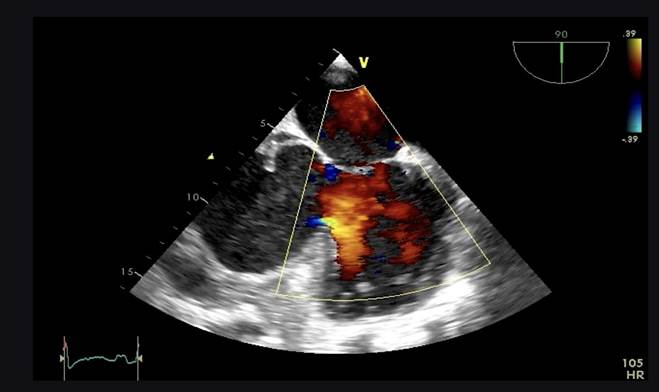

Aproximadamente 3 Semanas posterior al alta presenta cuadro de insuficiencia respiratoria asociado a insuficiencia cardiaca descompensada por lo que acude a nuestro Hospital de Especialidades Abel Gilbert Pontón siendo internada en Unidad Coronaria, a su ingreso se evidencia dolor precordial y torácico bilateral que irradia a región dorsal acompañado de disnea clase funcional NYHA IV/IV, tos persistente y edema leve de miembros inferiores, los laboratorios realizados evidencian anemia leve con hb 10.8 g/dL, péptido natriurético elevado de 12895 pg/ml, enzimas cardiacas negativas, hematuria y proteinuria en uroanálisis; en la radiografía de tórax se muestra cardiomegalia y derrame pleural bilateral; En electrocardiograma taquicardia sinusal, dextrorrotación, complejo QS en cara inferior, sin alteraciones de la onda T y segmento ST. En eco de pleura muestra derrame pleural derecho de moderada a gran cuantía y derrame pleural izquierdo moderado, sospechando de colagenopatía vs enfermedad autoinmune a descartar. Se realiza ecocardiograma transtorácico se evidencia formación aneurismática del VI de 9.5cm x 9.7cm tapizado por trombos con pérdida de la continuidad a nivel perimembranoso septal, además de una miocardiopatía dilatada con FEVI (fracción de eyección del ventrículo izquierdo) 28%. El estudio de líquido pericárdico da como resultado exudado con relación líquido/sérica de LDH 1,8 y proteína 0,7. En ecocardiograma transesofágico (Ilustración 1,2,3) se confirma pseudoaneurisma de gran tamaño del VI en región basal posterior con flujo bidireccional de 10 cm x 7,22cm tapizado de formación trombótica con pérdida de la continuidad de la región basal y posterior del VI con hipocinesia global e hipertensión pulmonar leve con insuficiencia mitral y tricuspidea leve por lo que se decide resolución quirúrgica.

Ilustración 1 Ecocardiograma Transesofágico. Pseudoaneurisma del VI en su porción septal

Fuente: Hospital de Especialidades Guayaquil “Doctor Abel Gilbert Pontón”.

Autor: Dra. María Sánchez Sánchez.